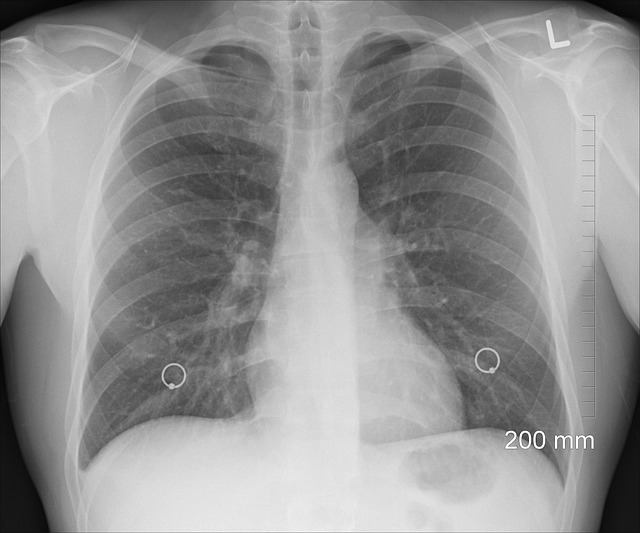

๋ณ๊ธฐ๋ณ ์์กด์จ๊ณผ ์ํ

๋น์์ธํฌ์ฑ ํ์์ ์กฐ๊ธฐ ๋ฐ๊ฒฌ ์ฌ๋ถ์ ๋ฐ๋ผ ์์กด์จ์ด ํฌ๊ฒ ๋ฌ๋ผ์ง๋๋ค. ์๋๋ ํ๊ท ์ ์ธ ์์น๋ฅผ ๊ธฐ๋ฐ์ผ๋ก ํ ๋ณ๊ธฐ๋ณ 5๋ ์์กด์จ์ ๋๋ค:

- 1๊ธฐ: 60~75%

- 2๊ธฐ: 40~55%

- 3๊ธฐ: 20~35%

- 4๊ธฐ: 5~10%

์กฐ๊ธฐ ๋ณ๊ธฐ์์์ ์์กด์จ์ด ๋์ ์ด์ ๋ ์์ ์ด ๊ฐ๋ฅํ๊ณ , ์ ์ด ์ ๋จ๊ณ์ด๊ธฐ ๋๋ฌธ์ ๋๋ค. ๋ฐ๋ฉด, 4๊ธฐ์ฒ๋ผ ์ ์ ์ ํผ์ง ๊ฒฝ์ฐ์๋ ์์กด์จ์ด ๋ฎ์ง๋ง, ์ต๊ทผ ์ ์ฝ ๋๋ถ์ ๋ฌด์งํ ์์กด๊ธฐ๊ฐ์ด ๊ณผ๊ฑฐ๋ณด๋ค ํฌ๊ฒ ๋์ด๋ ๊ฒ๋ ์ฌ์ค์ ๋๋ค.